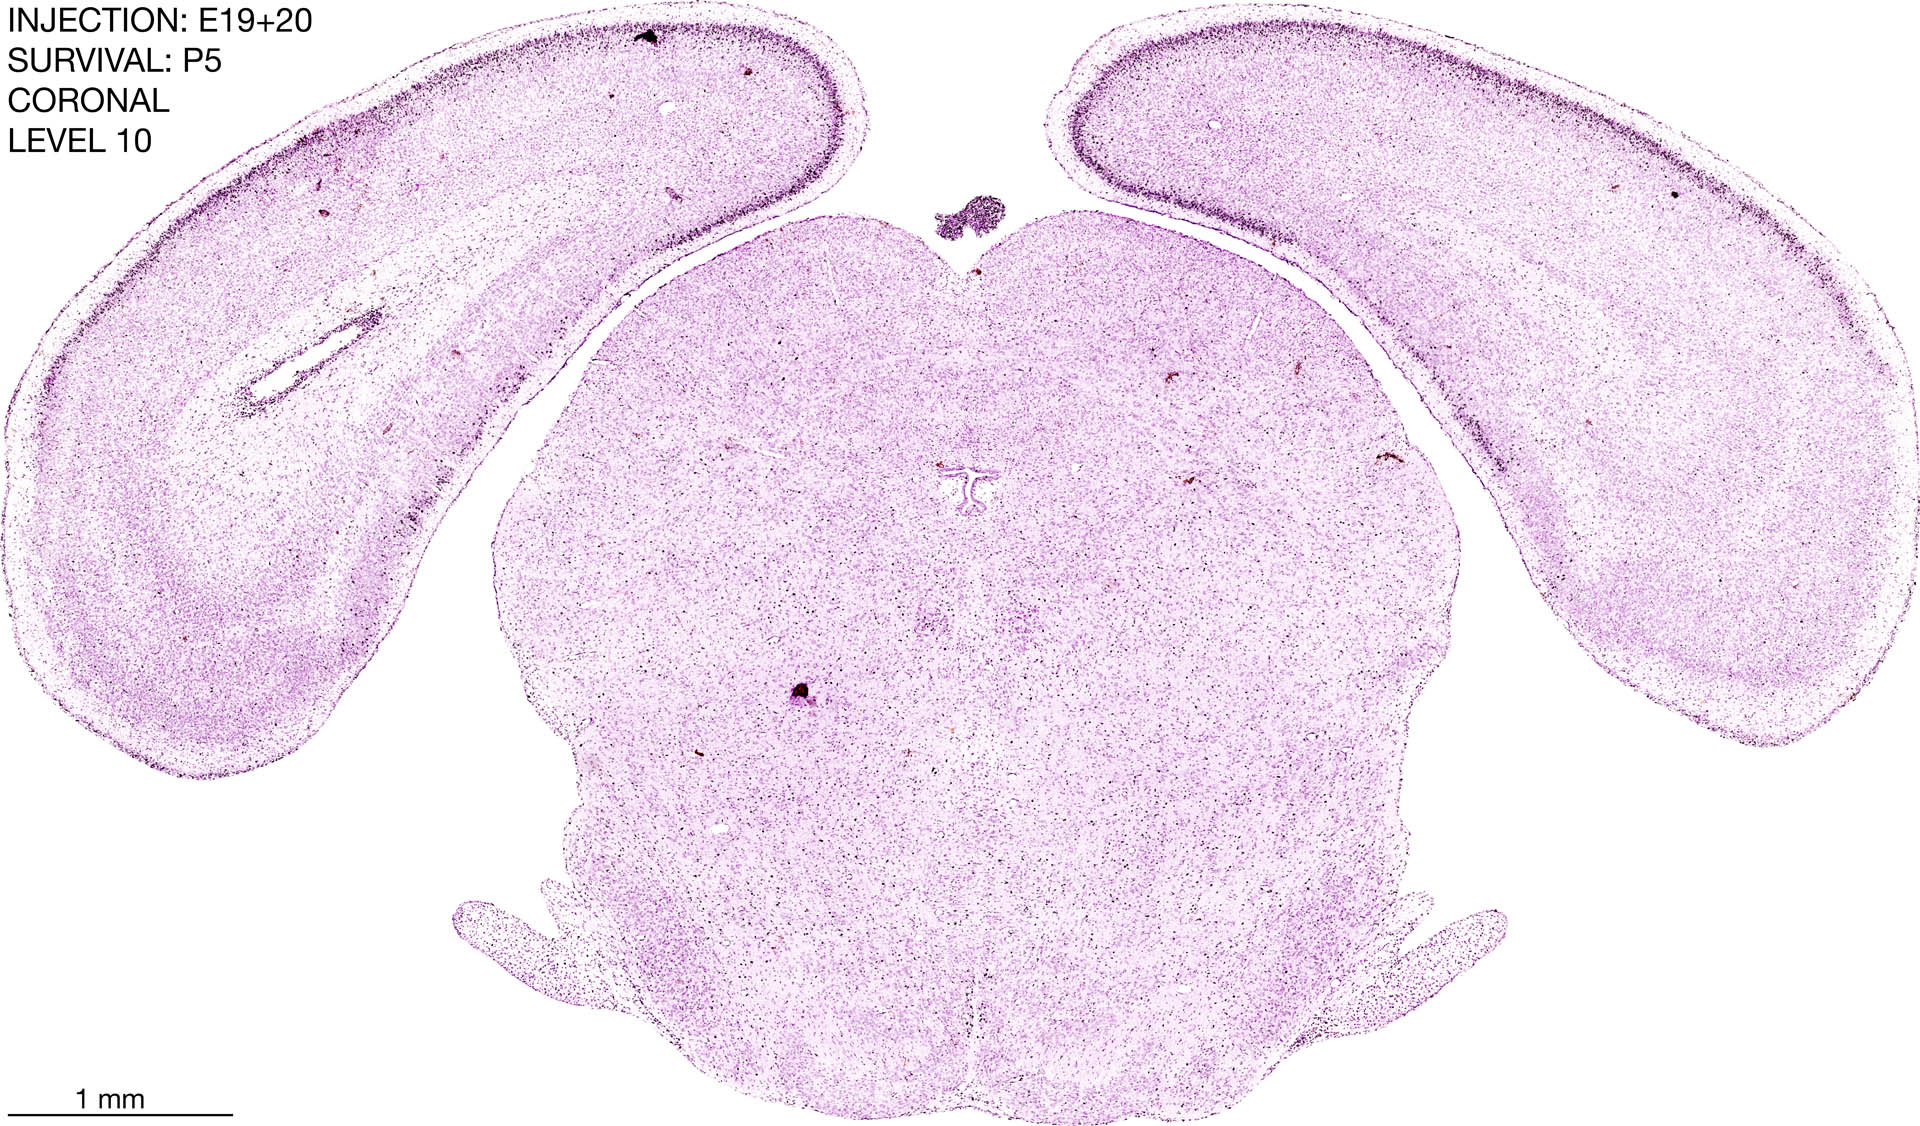

E19+20 P5 Survival The images below are from the brain of a rat that was exposed to tritiated thymidine on E19+20 and survived to P5. Download: Large | High Res Download: Large | High Res Download: Large | High Res Download: Large | High Res Download: Large | High Res Download: Large | High Res Download: Large | High Res Download: Large | High Res Download: Large | High Res Download: Large | High Res Download: Large | High Res Download: Large | High Res Download: Large | High Res Download: Large | High Res Download: Large | High Res Download: Large | High Res Download: Large | High Res Download: Large | High Res Download: Large | High Res Download: Large | High Res Download: Large | High Res Download: Large | High Res Download: Large | High Res Download: Large | High Res Download: Large | High Res Download: Large | High Res Download: Large | High Res Download: Large | High Res